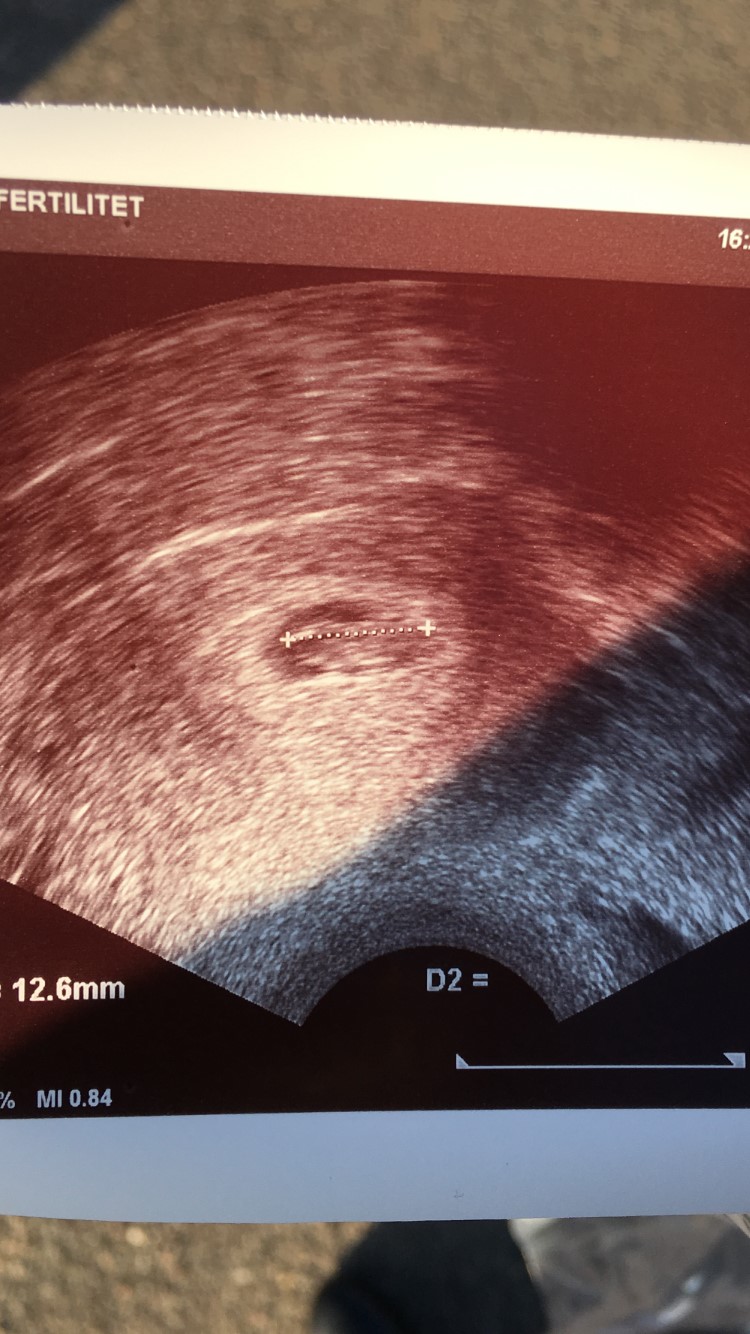

Efter 4,5 år i behandling nåede vi dertil, hvor vi så et bankede hjerte banke derudaf.

Det er det største nogensinde - og selvom det aldrig er nogen garantier, er jeg overbevist om, at det endelig er vores tur nu

jeg blev rykket 2 dage frem, så jeg er 7+6 idag